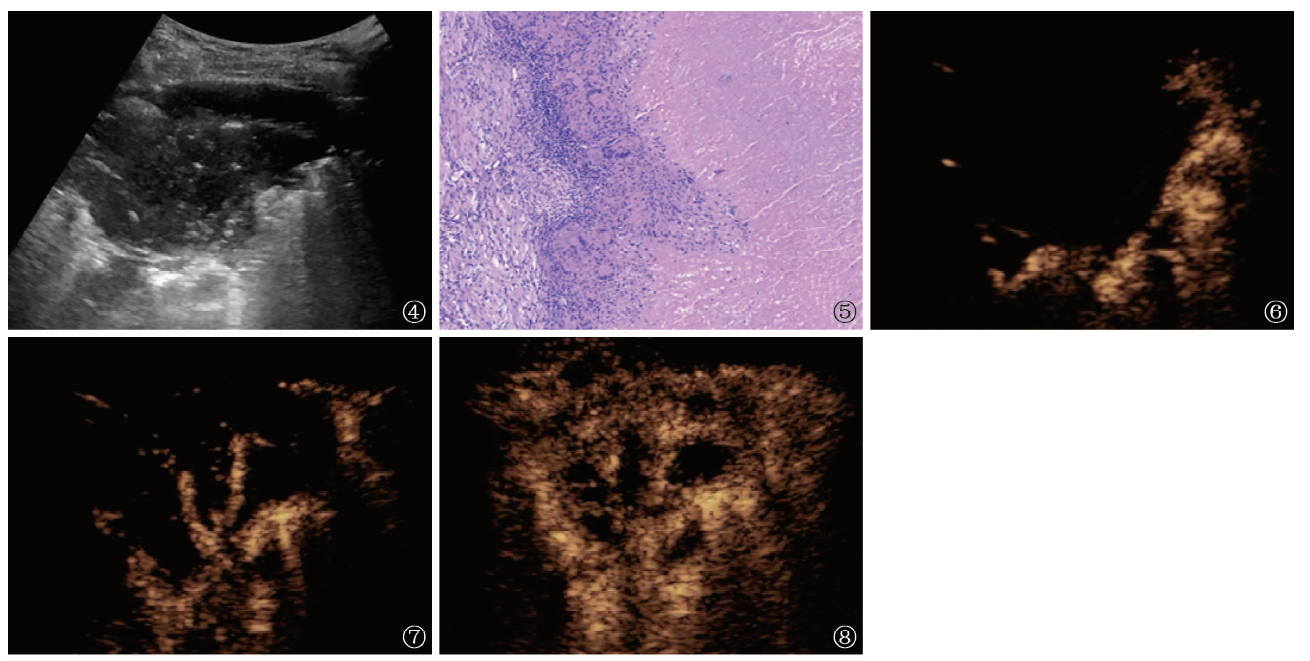

Objective To investigate the value of conventional ultrasound combined with contrast-enhanced ultrasonography in the differential diagnosis of pleural-based pulmonary tuberculosis and bacterial pneumonia.Methods A total of 35 patients with pulmonary tuberculosis (tuberculosis group) and 16 cases with bacterial pneumonia (pneumonia group) diagnosed by pathology, bacteriology or diagnostic therapy in Shanghai Pulmonary Hospital from January to May 2019 were enrolled. Conventional and contrast-enhanced ultrasound images of lesions between the two groups were analyzed, and the size, location, shape, echogenicity, enhancement pattern, arrival time, time to peak, clearance speed, incidence and characteristics of necrosis were compared.Results (1) Conventional ultrasound showed 28 cases (80.00%) with wedge shape, 5 cases (14.29%) with round-like shape, and 2 cases (5.71%) with irregular shape in the tuberculosis group; and 10 cases (62.50%) with wedge shape, and 6 cases (37.50%) with round-like shape in the pneumonia group, without significant difference between the two groups (χ2=4.109, P=0.128). There was hyperechoic between the deep lesion and the normal lung tissue, among which, “fragment sign” appeared 11 cases (31.43%) in the tuberculosis group and 13 cases (81.25%) in the pneumonia group, with the significant difference between the two groups (χ2=10.940, P=0.001); “Waterfall sign” appeared in 22 cases (62.86%) in the tuberculosis group and 3 cases (18.75%) in the pneumonia group, with the significant difference between the two groups (χ2=8.548, P=0.003). (2) Contrast-enhanced ultrasonography showed that arrival time of lesions was (8.43 (4.79,10.83)) s in the tuberculosis group and (7.80 (5.51,12.26)) s in the pneumonia group, without the significant difference between the two groups (U=0.721, P=0.471); arrival time difference between lesion and lung tissue was (1.47 (0.56,2.01)) s in the tuberculosis group and (2.00 (1.28,2.67)) s in the pneumonia group, without the significant difference between the two groups (U=1.453, P=0.146); peak intensity was (-41.89±5.72) dB in the tuberculosis group and (-44.89±5.72) dB in the pneumonia group, without the significant difference between the two groups (t=1.738, P=0.089); half time of intensity descent was (153.33 (124.02,180.00)) s in the tuberculosis group and (138.45 (128.70,147.09)) s in the pneumonia group, without the significant difference between the two groups (U=1.326, P=0.185). Necrosis occurred in 29 cases (82.86%, 29/35) in the tuberculosis group and 5 cases (31.25%, 5/16) in the pneumonia group, with the significant difference between the two groups (χ2=13.160, P=0.000). In terms of the characteristics of necrosis, 15 cases (51.72%, 15/29) presented with multiple non-interconnected sieve-like necrosis, 11 cases (37.93%, 11/29) presented with large patchy necrosis with regular shape and regular inner wall, and 3 cases (10.35%, 3/29) presented with almost total necrosis with circular enhancement of residual active margin in the tuberculosis group; 1 case (1/5) presented with large patchy necrosis with regular shape and regular inner wall, and 4 cases (4/5) presented with small patchy necrosis with regular shape and regular inner wall in the pneumonia group. There was significant difference between the two groups (χ2=26.692, P=0.000).Conclusion Conventional ultrasound shows the characteristic of “irregular fragment-like” hyperechoic behind the lesions of bacterial pneumonia. Contrast-enhanced ultrasonography shows that the incidence of necrosis in pulmonary tuberculosis is significantly higher than that in bacterial pneumonia, with the characteristics of “sieve-like” and “regular large patch” necrosis. These founds can provide diagnostic basis for the differential diagnosis.